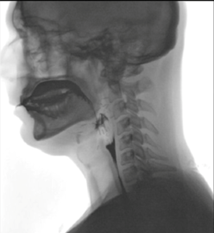

Η διαδικασία της κατάποσης είναι σημαντική για τη θρέψη και την ενυδάτωση του ανθρώπου και παίζει πρωταρχικό ρόλο στη διατήρηση τόσο της καλής μας υγείας όσο και της ποιότητας ζωής μας. Ο μηχανισμός της κατάποσης εμφανίζεται στην εμβρυϊκή ηλικία των τριών μηνών, επιτρέποντας στο έμβρυο να καταπίνει αντανακλαστικά το αμνιακό υγρό (βλ. παρακάτω εικόνες).

Η κατάποση είναι μια πολύπλοκη και δυναμική αισθητικοκινητική ενέργεια που περιλαμβάνει τη συγχρονισμένη και διαδοχική ενεργοποίηση και καταστολή 26 ζευγών διαφορετικών μυών της στοματικής, φαρυγγικής, λαρυγγικής και οισοφαγικής κοιλότητας. Παραδοσιακά, αν και καταχρηστικά λόγω της πολυπλοκότητάς της, η διαδικασία της κατάποσης υποδιαιρείται και μελετάται σε τέσσερις διαφορετικές φάσεις: προπαρασκευαστική – στοματική – φαρυγγική – οισοφαγική. Στην προπαρασκευαστική φάση, η τροφή συνθλίβεται και τοποθετείται σε βέλτιστη θέση εντός της στοματικής κοιλότητας για να προωθηθεί προς στον φάρυγγα. Στη στοματική φάση, η στοματική κοιλότητα καθαρίζεται από υπολείμματα τροφής και ο πλέον σχηματισμένος βλωμός προωθείται στον φάρυγγα. Στη φαρυγγική φάση της κατάποσης, με εξασφαλισμένη την προστασία της μύτης και του λάρυγγα, ο βλωμός προωθείται γρήγορα προς τον οισοφάγο. Τέλος, στην οισοφαγική φάση ο βλωμός μεταφέρεται στο στομάχι.